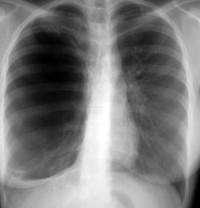

Ακτινολογική εικόνα πνευμοθώρακα

- Η ακτινογραφία θώρακα η οποία πρέπει να γίνεται πάντα σε όρθια θέση (επειδή κατά την ύπτια κατάκλιση η προς τα άνω μετακίνηση του αέρα και η προσέγγιση των δύο πετάλων του υπεζωκότα προς τα πλάγια μπορεί να επισκιάσουν την παρουσία του) αποκαλύπτει εμφανές όριο του σπλαχνικού υπεζωκότα χωρίς σκιαγράφηση πνευμονικού ιστού μεταξύ του ορίου αυτού και του θωρακικού τοιχώματος καθώς και μετακίνηση του μεσοθωρακίου και παρέκκλιση της τραχείας προς την υγιή πλευρά.

- Στον ύπτιο ασθενή με φαινομενικά φυσιολογική ακτινογραφία αλλά με υποψία πνευμοθώρακα αναζητούμε στην ακτινογραφία μια ασυνήθη (κάθετη) απεικόνιση του καρδιακού ορίου ή του διαφράγματος με αυξημένη διαυγαστικότητα των γειτονικών τμημάτων του θώρακα και της κοιλιάς, μια κάθετη γραμμή παράλληλη προς το θωρακικό τοίχωμα (από έλξη του μέσου λοβού από το θωρακικό τοίχωμα) ή μια διαγώνια γραμμή από την καρδιά στην υποδιαφραγματική γωνία.

- Η ακτινογραφία σε περίπτωση υποψίας μικρού πνευμοθώρακα πρέπει να γίνεται κατά το τέλος της μέγιστης εκπνοής ενώ στην περίπτωση που ο πνευμοθώρακας συνοδεύεται από διάσπαση συμφύσεων της υπεζωκοτικής κοιλότητας μπορεί να εμφανιστεί αιμοπνευμοθώρακας με υδραερικό επίπεδο στην υπεζωκοτική κοιλότητα.